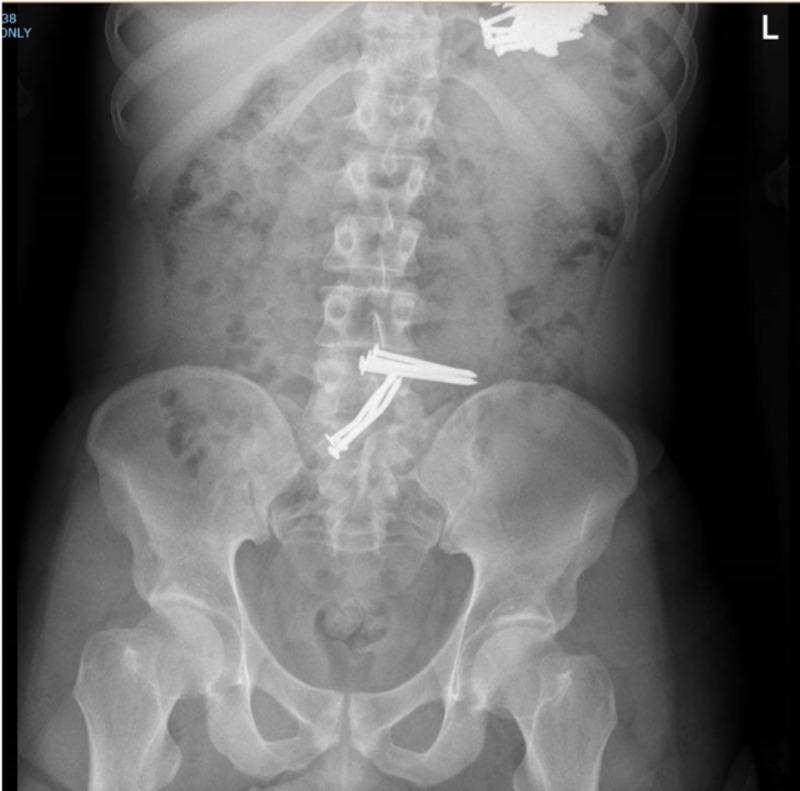

Ingestion of foreign bodies is common within the pediatric population; in adults, it occurs more commonly in those with a psychiatric background. Diagnosis of such cases can be readily made based on plain abdominal X-rays. As reported, many foreign bodies pass through the gastrointestinal tract without complications, obstruction, bleeding, and perforation. The ultimate decision of the best management approach for such cases should be made based on the available expertise as well as the patient's specific factors. Observation, endoscopic removal, and surgical intervention are all acceptable approaches in cases of metal foreign body ingestion. We report a case of a 29-year-old male patient brought to the emergency department following ingestion of multiple sharp nails. He underwent surgical exploration, which resulted in the retrieval of 73 metallic nails.

吞食异物在儿科人群中很常见;在成人中,吞食异物在有精神病史的人群中更为常见。此类病例的诊断可根据腹部平片轻松做出。据报道,许多异物可通过胃肠道而不出现并发症、梗阻、出血和穿孔。对于此类病例,最佳治疗方法的最终决定应基于现有的专业知识以及患者的具体因素。在金属异物吞食病例中,观察、内镜取出和手术干预都是可接受的方法。我们报告一例29岁男性患者,因吞食多根尖锐钉子被送往急诊科。他接受了手术探查,结果取出了73根金属钉子。